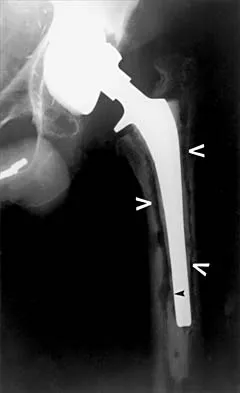

Figure 7 shows the AP radiograph of a 60-year-old man who has had pain in the thigh for past 6 months. History reveals that he underwent hip replacement 1 year ago. The radiographic changes are most likely the result of what process?

Explanation

The arrows in the radiograph point to circumferential radiolucencies that strongly support the diagnosis of septic loosening. Radiolucent lines that occur in such a short time are also typical of an infection. Garvin KL, Hanssen AD: Infection after total hip arthroplasty: Past, present, and future. J Bone Joint Surg Am 1995;77:1576-1588.